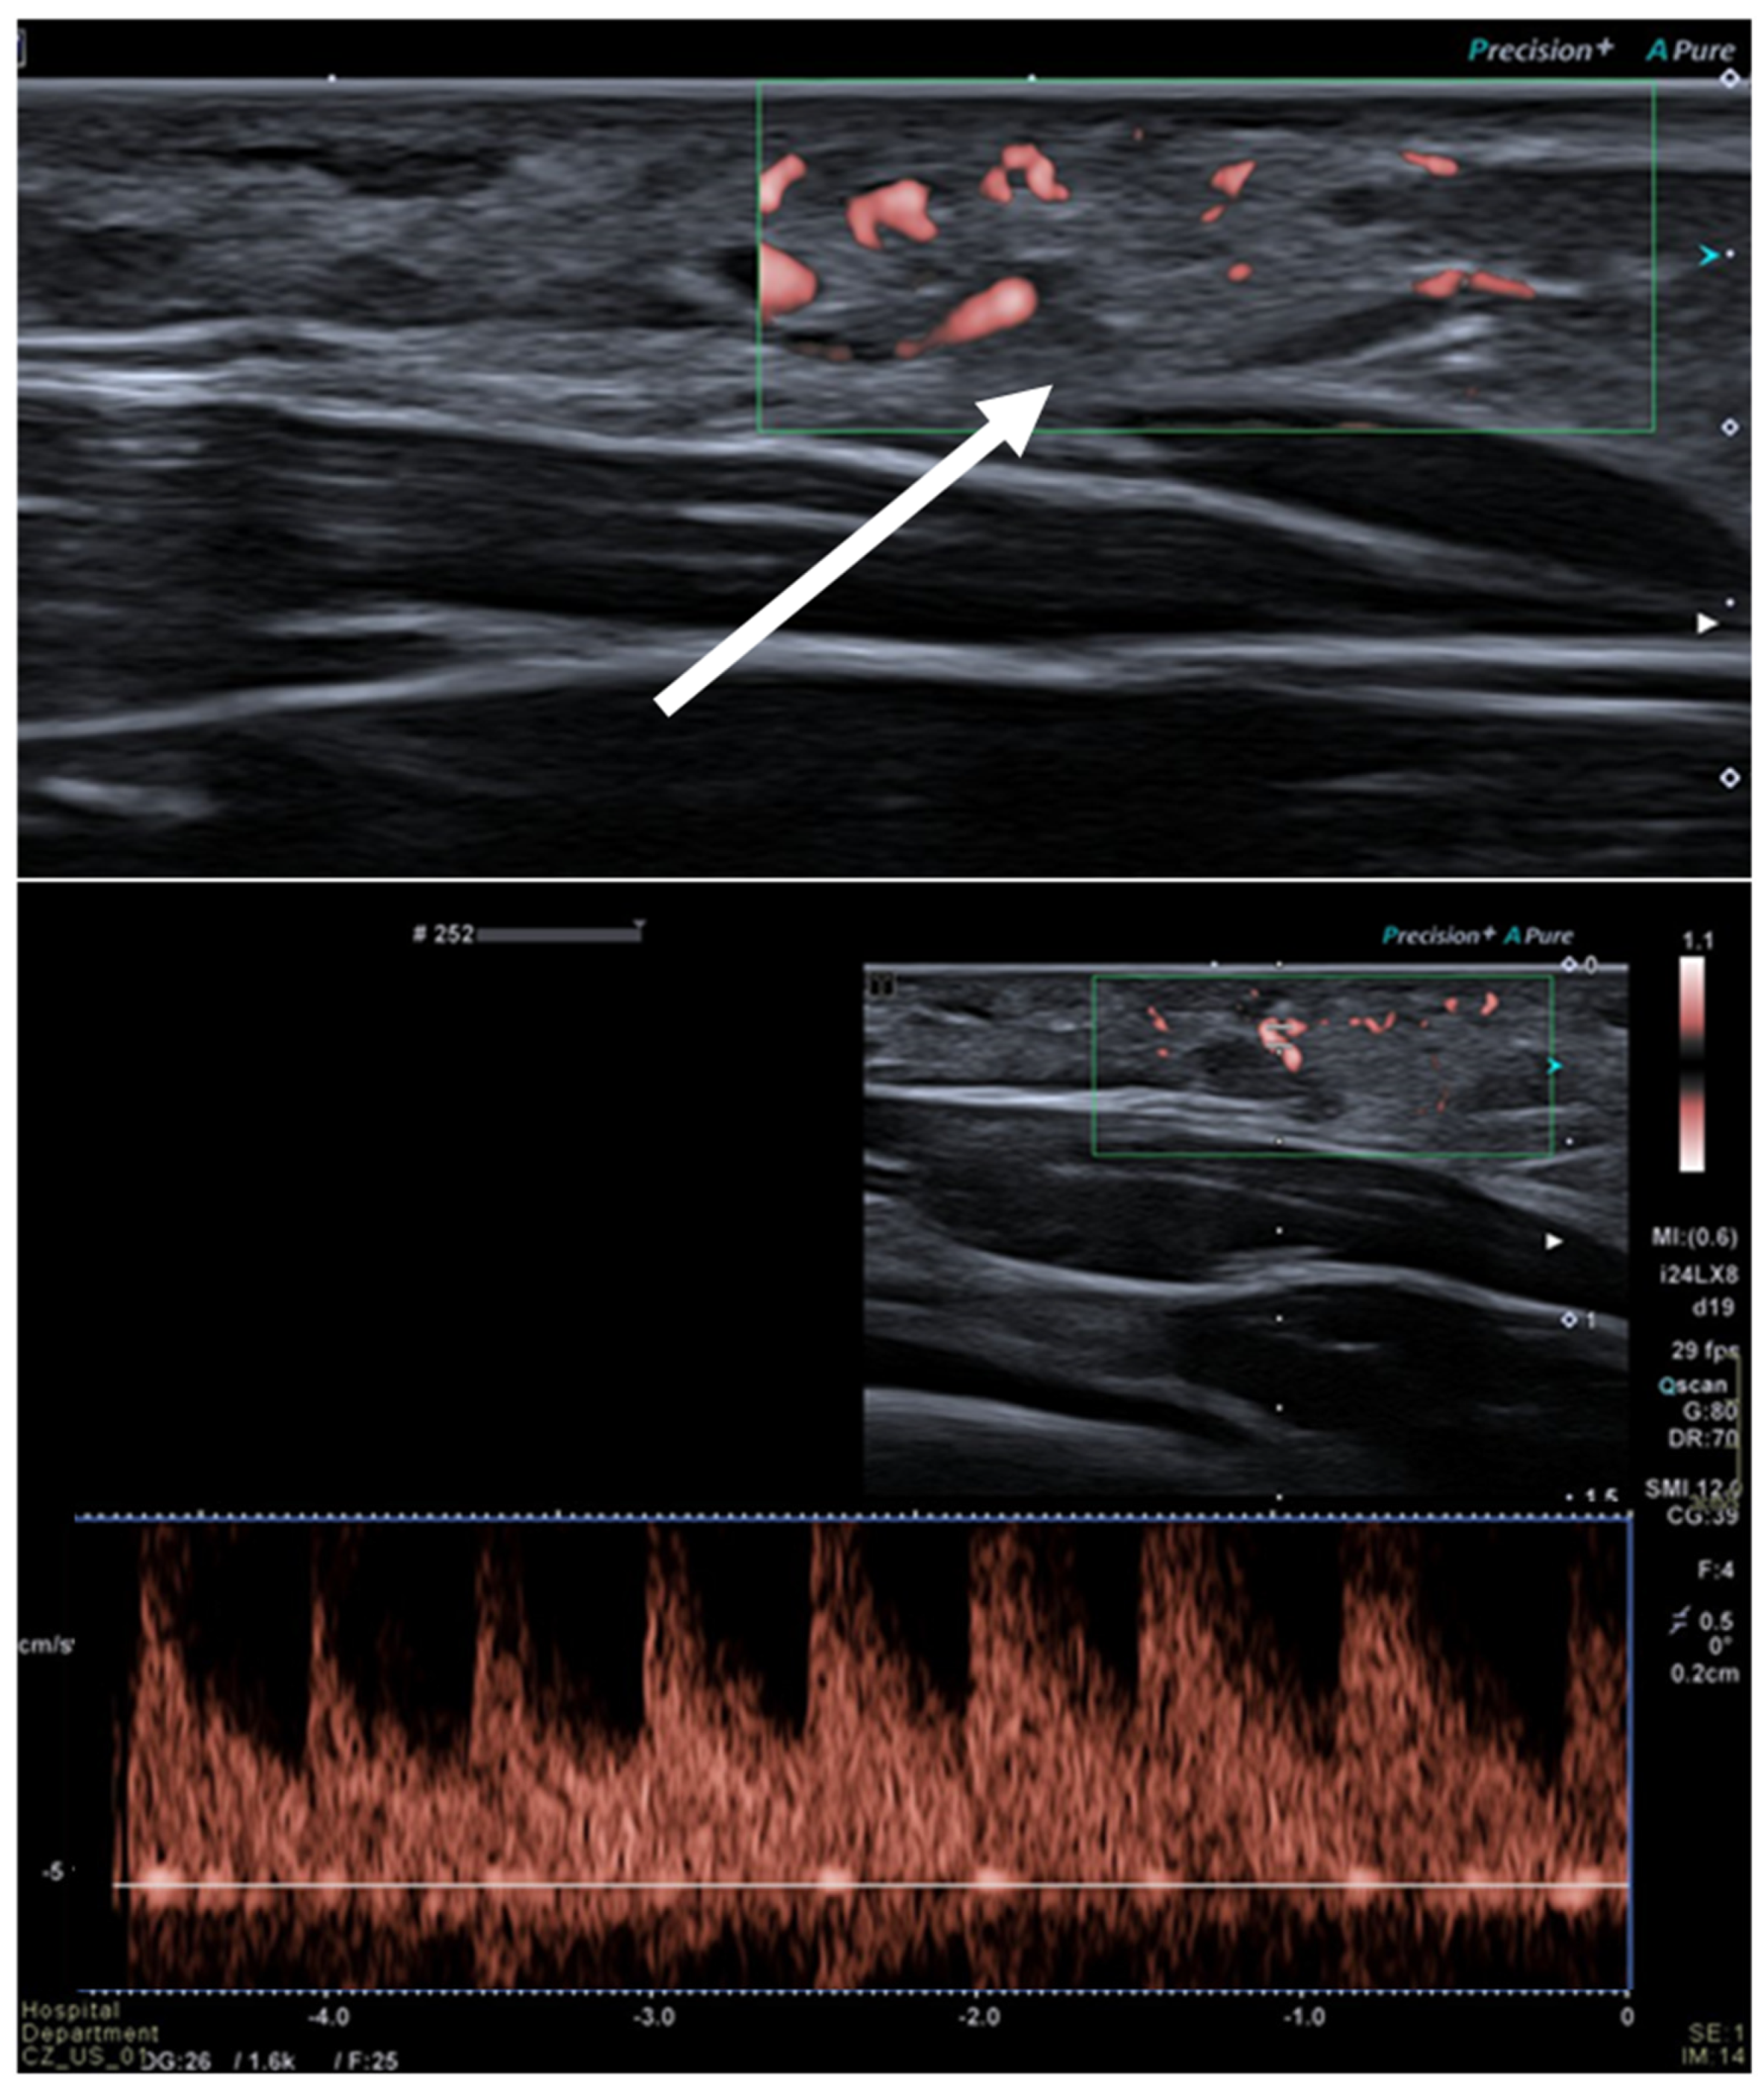

2.3. Hemangioma

| Hemangioma |

|